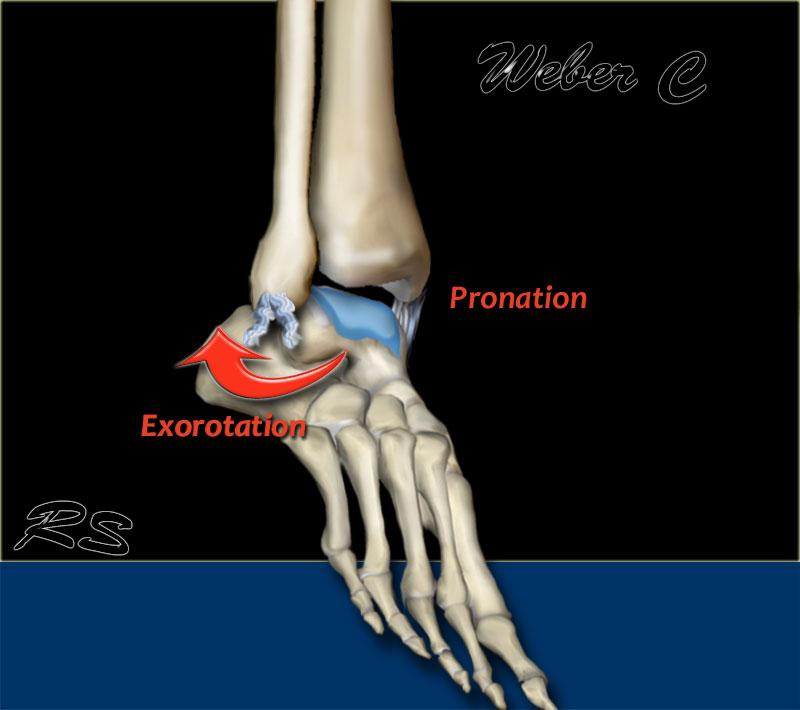

Weber C

Đây là gãy xương ở trên mức khớp chày mác. Thường có đứt hoàn toàn khớp chày mác kèm theo mất vững khớp cổ chân.

Theo Lauge-Hansen, đây là kết quả của lực xoay ngoài tác động lên bàn chân ở tư thế ngửa.

- Giai đoạn 1 – Gãy giật mắt cá trong

hoặc – đứt dây chằng - Giai đoạn 2 – Đứt khớp chày mác trước

- Giai đoạn 3 – Gãy xương mác ở trên mức khớp chày mác (đây là gãy Weber C thực sự)

- Giai đoạn 4 – Gãy giật mắt cá sau

hoặc – đứt khớp chày mác sau